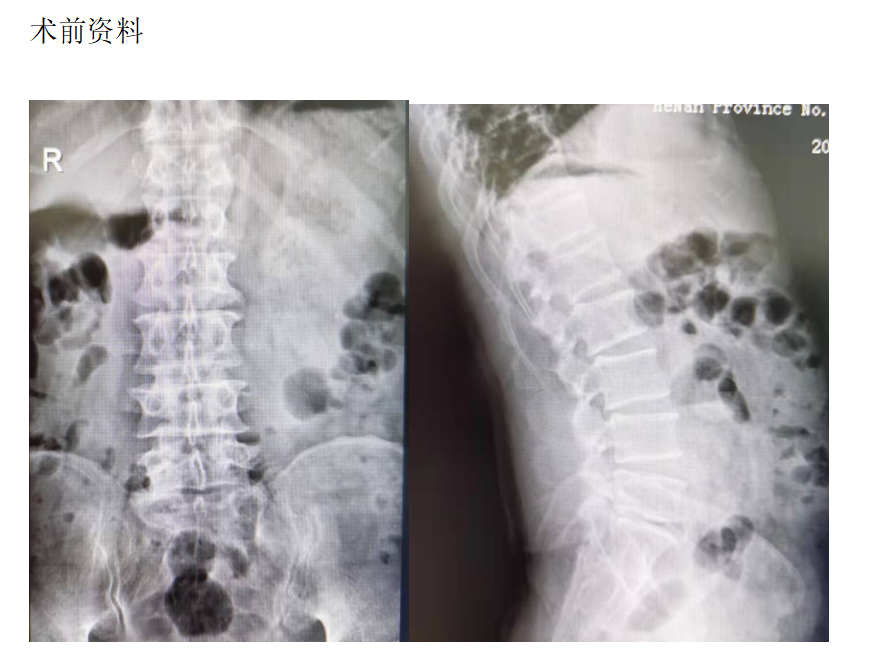

主诉:腰部疼痛3年,加重伴双下肢疼痛麻木1年

现病史:3年前出现腰部疼痛、酸困,无下肢疼痛麻木不适,弯腰活动受限,行走及站立时疼痛加重,平卧休息稍减轻,未治疗,上述症状持续加重,近1年来又出现双下肢疼痛麻木,以左侧为著,步行困难,步行能力约100米,为求诊治,现来我院,遂以“腰椎管狭窄症”为诊断收住我科。发病以来,饮食正常,睡眠一般,体力正常,大小便正常。